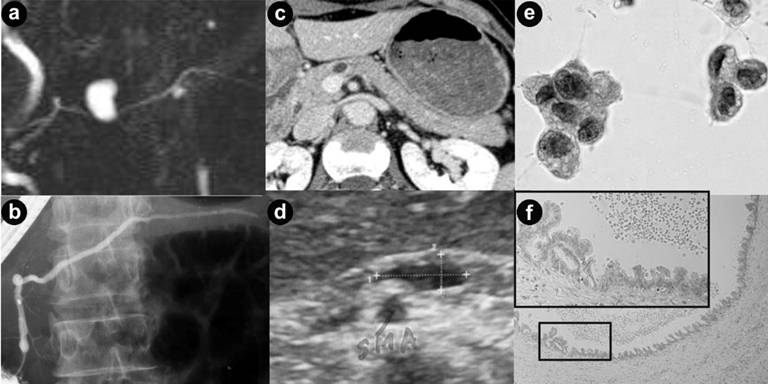

Another test for predicting malignancy in IPMN is cytologic examination of pancreatic juice. We had reported for the first time that pancreatic juice cytology was a predictor of malignancy in IPMN, when it was called mucin producing tumor of the pancreas [26]. However, later investigations could not reproduce a promising result like ours [27] but yielded only low sensitivities for malignancy, where calculation was performed in all IPMNs including MD-IPMNs and BD-IPMNs [10, 28]. In contrast, studies that calculated sensitivities of cytology individually in MD-IPMNs and BD-IPMNs yielded higher sensitivities in the former and lower ones in the latter [24, 29, 30]. Especially, Yamaguchi reported a high sensitivity of 80% in MD-IPMNs by collecting materials directly using peroral pancreatoscopy, which was a procedure similar to ours that had been published [27], and a low sensitivity of 42% chiefly in BD-IPMNs using catheter alone [30]. Results of these reports indicated that higher sensitivities of pancreatic juice cytology were yielded only by acquiring specimens directly from the neoplasms in MPD, whereas lower sensitivities were produced because malignant cells were not aspirated directly but sampled using a catheter placed in MPD that communicated with dilated branch ducts harboring neoplasm. In order to improve the diagnostic accuracy of pancreatic juice cytology in BD-IPMNs, it is important to obtain a sufficient volume of mucous pancreatic juice and to identify a few malignant cells among a vast majority of benign adenomatous cells in the specimen [26]. In the present study, significance of cytology was the identification of malignant BD-IPMNs that was not detected by mural nodule size ≥10 mm. A sensitivity of 50% by mural nodule size alone increased to 88% without lowering specificity by diagnosing BD-IPMNs with mural nodules <10 mm as malignant when they had positive results of cytology. Despite its low sensitivities reported, one of the predictors of malignancy in BD-IPMN is positive cytology in pancreatic juice [13, 29, 31], which is recommended in its management (Figure 3).

|

Figure 3. A representative case of malignant IPMN with nodule size of ≥10 mm in size and negative cytology. (a). Magnetic resonance pancreatography (MRP) showed a cyst of 15 mm in size at the pancreatic body and the diffuse dilated main pancreatic duct. (b). Endoscopic retrograde pancreatography (ERP) showed a filling defect in the cyst and peri-cystic area which indicated presence of mucus. Tip of the catheter used for aspiration of pancreatic juice was inserted into the cyst. (c, d). CT and endoscopic ultrasound showed a mural nodule of 15 mm in size inside the cyst. (e). Microscopic examination of pancreatic juice revealed hyperplastic cells which were classified into class II (Papanicolaou’s stain). Despite negative cytological result, the patient underwent surgery because of mural nodule of ≥10 mm in size. (f). Final diagnosis was determined as non-invasive intraductal papillary mucinous carcinoma by microscopic examination of the resected specimens. A mural nodule consisted of carcinomatous epithelia was observed inside the cyst at the pancreatic body. |